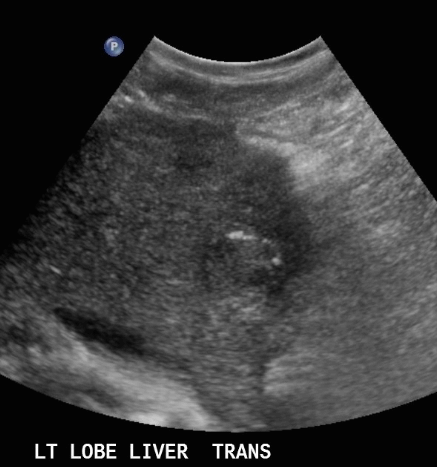

암부위와 정상조직의 경계가 뚜렷한 것을 말한다. 종양 내에 섬유성의 격벽이 존재하며 이것에 의해 소결절로 다시 구분된다. 간세포암의 초음파상은 직경 3cm 이상의 결절형이 특징적이며 저에코의 격벽과 경계가 되는 에코레벨이 다른 소결절이 모자이크 패턴(mosaic pattern)으로 관찰되며 피막에는 달무리(halo)가 존재한다.

① <2cm small hcc sono finding

- well define

- round shape

- hypoechoic / hyperechoic, bright loop sing pattern (지방화, 탈분화 동반 경우 드물게 보임)

- irregular / indistinct margin

- halo (-)

<2cm small hcc sono features ② 2~3cm hcc sono finding

- hypo-hyperechoic

- ireegular margin

- halo(+) 종양이 2cm 이상 커지면 주위조직을 밀게 되면서 피막이 형성되면서 저에코 테두리가 나타남. (간세포암의 40~50%)

2~3cm hcc sono features ③ 3~5 cm hcc sono finding

- heterogenous

- irregular

- hump sign (표면에 존재하는 결절형 종괴에서 간표면으로 종괴가 돌출하는 경우 나타난다)

- mosaic pattern (종양내부에 괴사나 출혈이 생겨 내부에 균열이 있는 것처럼 보이는 모자이크패턴이 나타남)

- color doppler : internal mass pattern (feeding artery)